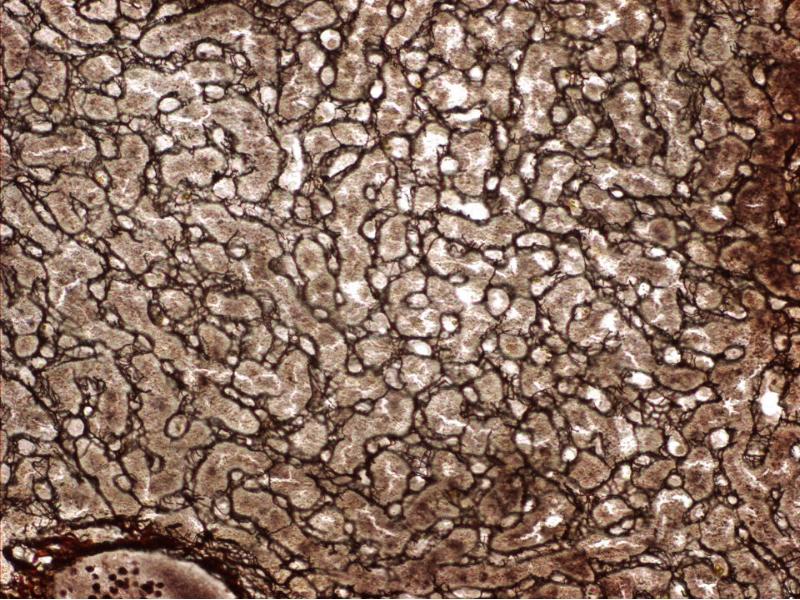

Spleen

Red pulp White pulp

Connective tissue

Sinusoids

Blood

Lymphocytes